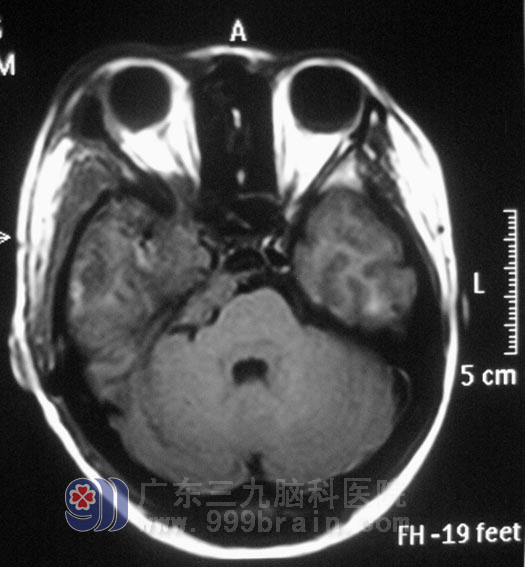

小李在2008年高考那年,出现右眼视力下降,以为是高负荷的复习迎考,造成视力出现问题。一年前右耳听力开始进行性下降,前十多天又出现了右耳失聪,外院行头颅MR检查提示:右侧眶内、中颅窝底、岩斜区占位,病变大小4.98cm×3.34cm×2.62cm,主要位于中颅窝,小部分累及后颅窝,脑干受压。

广东三九脑科医院综合神经外科 鲁明主任查阅影像资料发现:肿瘤侵润海绵窦,颅内外沟通,经CT检查见蝶骨及斜坡右侧、右侧颞骨岩部、额骨底部右侧骨质异常,经耳鼻喉科活检排除鼻咽癌。

13日,鲁主任主刀,在全麻下行右侧中颅窝、岩斜区占位切除术,术中显微镜下沿中颅窝肿瘤基底部开始切除,肿瘤质软,呈灰白色,夹杂黄色颗粒,血供丰富,沿基底部硬膜向内侧切除,电磁刀切开并切除小脑幕约1cm可见颞骨岩部、斜坡肿瘤组织,肿瘤与周围关系紧密,向内切除斜坡处肿瘤,向下见肿瘤与滑车、三叉神经粘连,抬起额叶,暴露视神经、颈内动脉及其分叉处,可见第二、三间隙内肿瘤,肿瘤向眶上裂内生长,予以钝性切除,手术历时10小时后顺利结束。病理结果为:脑膜瘤。